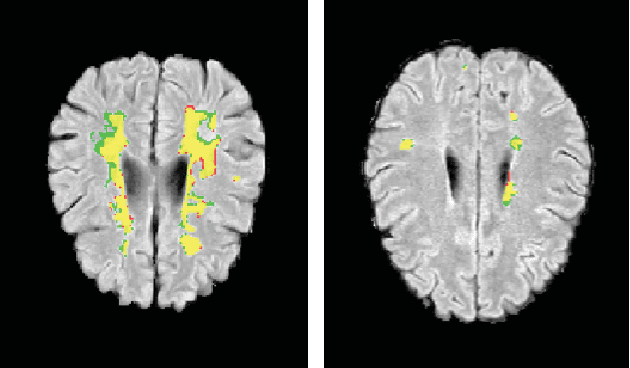

This paper explores the use of a soft ground-truth mask ("soft mask'') to train a Fully Convolutional Neural Network (FCNN) for segmentation of Multiple Sclerosis (MS) lesions. Detection and segmentation of MS lesions is a complex task largely due to the extreme unbalanced data, with very small number of lesion pixels that can be used for training. Utilizing the anatomical knowledge that the lesion surrounding pixels may also include some lesion level information, we suggest to increase the data set of the lesion class with neighboring pixel data - with a reduced confidence weight. A soft mask is constructed by morphological dilation of the binary segmentation mask provided by a given expert, where expert-marked voxels receive label 1 and voxels of the dilated region are assigned a soft label. In the methodology proposed, the FCNN is trained using the soft mask. On the ISBI 2015 challenge dataset, this is shown to provide a better precision-recall tradeoff and to achieve a higher average Dice similarity coefficient. We also show that by using this soft mask scheme we can improve the network segmentation performance when compared to a second independent expert.